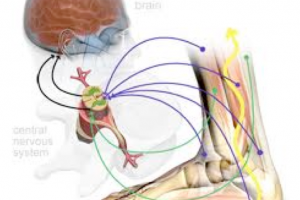

ももの前の筋肉が低下すると半月板を前側に動かすことが出来なくなり、結果的にひざの内側が痛くなります。

では、なぜひざの前側の筋肉である大腿四頭筋が筋力低下をするとひざの内側の痛みに繋がるのかを具体的に見ていきましょう。

もし、大腿四頭筋が筋力低下していたらそれらのパーツも働かなくなるので当然、半月板も動かないです。

本来はひざの関節が伸びると半月板は前に移動することで円滑な関節運動起きるのが、ももの骨とスネの骨に挟み込まれてしまい、痛くなるという公式が出来上がってしまいます。

その為、こういうケースでひざの内側に痛みがある場合もも前の筋肉を鍛えてひざ痛改善の効果は出ると思います。